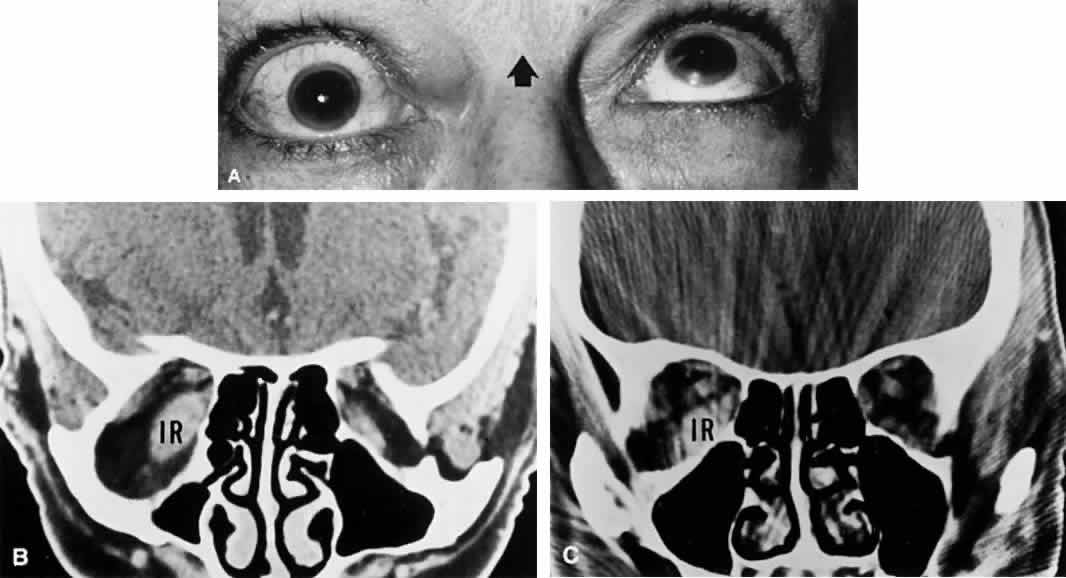

| Palsy of the superior oblique, as in the case of isolated lateral rectus

weakness, may be due to local orbital processes that should be distinguished

from a neurogenic lesion per se. As always, myasthenia and Graves

myopathy (an especially frequent cause of incomitant vertical strabismus) must

be suspected and appropriate tests performed. The pattern

of muscle imbalance and ocular versions can be quite similar in ipsilateral

inferior rectus fibrosis (e.g., in Graves disease) and contralateral superior oblique paresis50; however, worsening of the vertical deviation in upgaze is seen in inferior

rectus fibrosis, and in downgaze in superior oblique palsy. Also, intraocular

pressure may increase in attempted upgaze in restrictive (Graves) disease. Excyclodeviations are more prominent in superior oblique

paresis than in thyroid myopathy, which may show significant excyclotorsion

only in abduction. Superior oblique palsies may present spontaneously in late childhood and possibly represent “decompensated” congenital fourth nerve palsies. This diagnostic concept (i.e., that fusional mechanisms decompensate in later life) has also been applied to otherwise healthy adults with spontaneously acquired, unremitting superior oblique palsies of unknown origin (Fig. 9). A similar, often transient, occurrence of superior oblique palsy has been reported during pregnancy.51 These adults complain of reading difficulties, principally momentary diplopia, and show all of the attributes of superior oblique palsy. Old photographs may document tilting of the head, and further inquiry may uncover a forgotten history of childhood squint. Patients with congenital trochlear palsies commonly show increased amplitudes of vertical vergence.52 Normally, only 2 to 4 prism diopters (D) of vertical fusional amplitude are found, but patients with congenital superior oblique pareses may be able to fuse a 10-D or even a 30-D deviation. However, the presence of large vertical fusional amplitudes does not necessarily imply a congenital etiology, because vertical fusional vergence may increase in adults within weeks or months after an acquired vertical strabismus. The cause of most congenital superior oblique palsies is unknown; however, agenesis of the trochlear nucleus has been described in association with agenesis of other cranial-nerve nuclei,53 but never in the situation of an isolated congenital fourth nerve palsy. Dysplasia (aplasia) of cranial nuclei may occur after perinatal peripheral injuries to nerves, with secondary “dying back.” Also, axonal death, with selective elimination and preservation, is an established phenomenon during neurogenesis of all cranial nerves.54 Absence of the superior oblique tendon has been observed during surgery to correct putative isolated congenital superior oblique palsies. This phenomenon may be more common in patients with craniofacial dysostoses.55 Indeed, Helveston et al56 reported congenital absence of the superior oblique tendon in 18% of patients with congenital superior oblique palsy, in whom a tuck of the superior oblique had been contemplated, and in another subgroup of patients with congenital superior oblique pareses, abnormally lax superior oblique tendons have been described. Bilateral congenital superior oblique palsies (particularly asymmetric pareses), as with bilateral acquired superior oblique palsies, may initially appear to be unilateral until corrective surgery “unmasks” the contralateral palsy. Other than in the context of trauma, acquired isolated fourth nerve palsy occurs far less frequently than abducens or oculomotor palsies. In a retrospective study of 412 patients,57 third and sixth nerve palsies were seven times more common than fourth nerve palsy. As with isolated abducens palsy, many spontaneous trochlear palsies are classified as “unknown” or “vascular.” In the older age group, isolated fourth nerve palsy is frequently associated with diabetes. Keane58 provided an excellent overview of fourth nerve palsy among 215 patients, with head trauma representing the cause in more than 50%; no tumors showed isolated palsies, but were accompanied by other defects related to lesions in the cavernous sinus. In comparison, 149 patients with ocular myasthenia did not show isolated superior oblique palsies. Bilateral fourth palsies occurred in 19%; again, the majority of these cases were due to head trauma. Herpes zoster ophthalmicus may be associated with isolated trochlear palsy,59 with variable recovery, but meningitis produces other signs and symptoms.58 Although extremely rare, intracranial aneurysms (e.g., superior cerebellar artery) have been documented to cause superior oblique palsy as well.60 Autosomal-dominant inheritance of superior oblique palsy, some bilateral, is also documented.61 The causes of fourth nerve palsies are listed in Table 4.